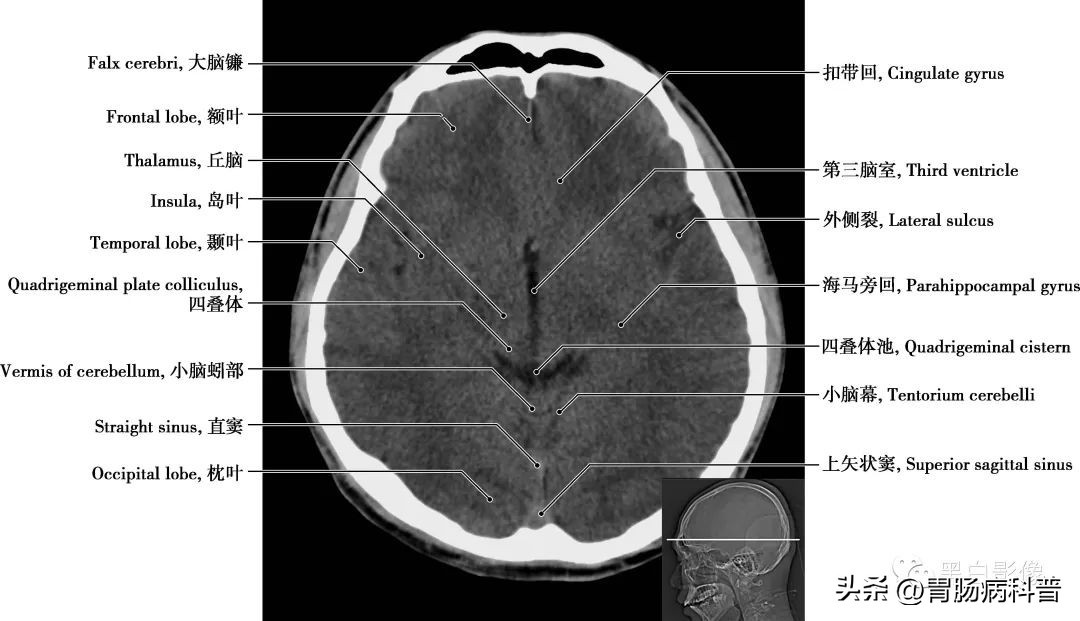

图1-1-11 经大脑脚轴位切面

中脑 介于间脑与脑桥之间,是视觉以及听觉的反射中枢。所有大脑皮层与脊髓间的上行及下行神经通路都经过中脑,同时通过白质与其他中枢神经系统的分部相联系。环池 在中脑外侧连接于四叠体池和脚间池之间,其内有大脑后动脉、小脑上动脉、脉络丛前动脉、脉络丛后动脉、基底动脉和滑车神经,为脑脊液循环的必经之路